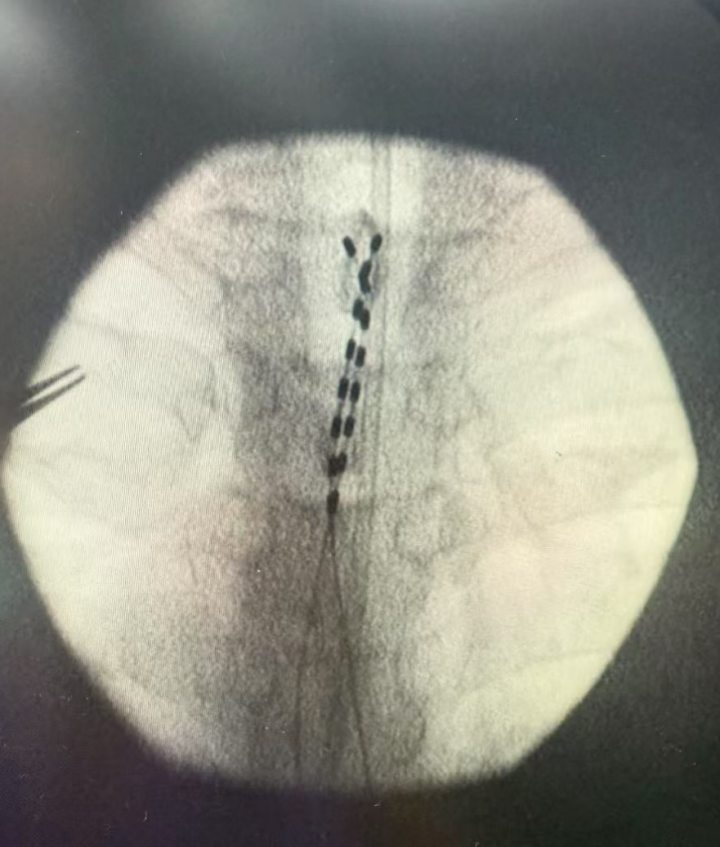

“那是一位58岁的男性患者,因2型糖尿病导致胃轻瘫、糖尿病性周围神经病变,因此双侧胸背部疼痛难忍,双下肢无力,另外他还有很多复杂的基础病。简单地说,我为他做了脊髓电刺激术,即在脊髓植入两根电极和脉冲发生器后,他疼痛缓解了90%以上。”

冯主任介绍,脊髓电刺激是通过微创手术,将一根细小的电极植入脊柱内,并连接一个体外的脉冲发生器,通过发放微弱电流来调节脊髓神经信号,阻止大部分疼痛信号上传到大脑,从而达到治疗慢性顽固性疼痛的疗法。

(冯主任在患者脊髓植入两根电极)

可以把它理解为一种针对神经系统的“起搏器”或“调音器”。

它的难点在于,电极植入的位置,要尽可能覆盖大片目标神经纤维,这很考验医生的能力。